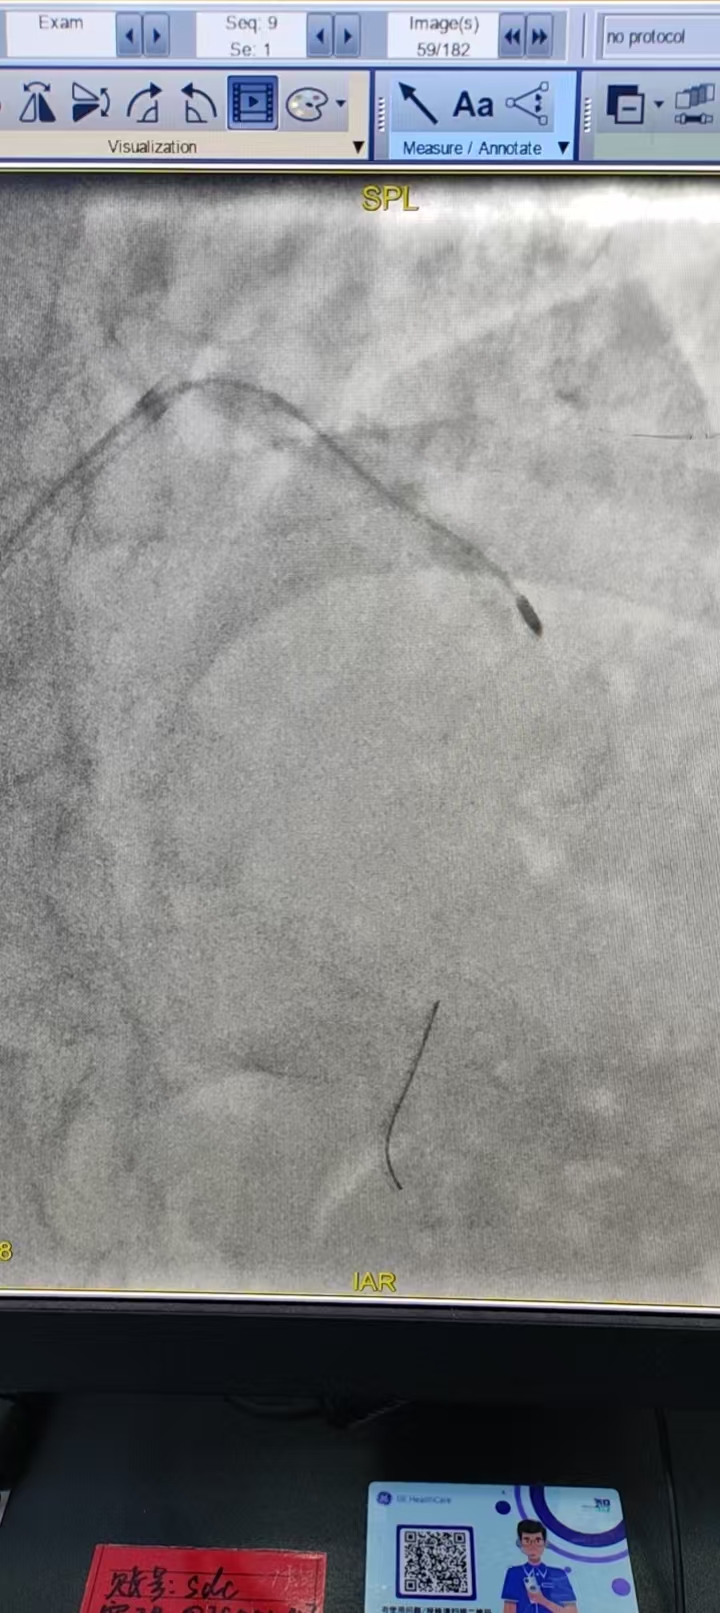

手术过程中,张家立主任团队凭借精湛的操作技术,顺利完成钙化病变旋磨修饰、震波球囊预处理及支架精准植入。

全程手术平稳顺利,术后患者胸痛、气短症状明显缓解,生命体征稳定,恢复情况良好,标志着此次区域首例新技术应用圆满成功!

△术后